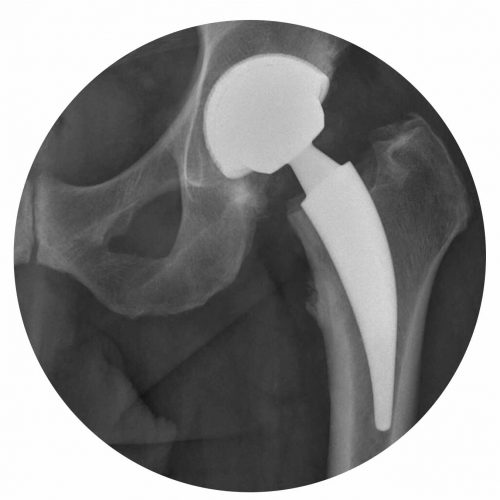

O mundo da ortopedia prepara-se para mais uma edição do 3.º HIP G.I.N. (Global Issue Network) Summit, um evento dedicado às grandes questões da cirurgia da anca. Organizado pelo Lusíadas Knowledge Center em parceria com a UpHill Events, o summit ocorrerá nos dias 21 e 22 de novembro de 2025, na Herdade da Comporta, reunindo…